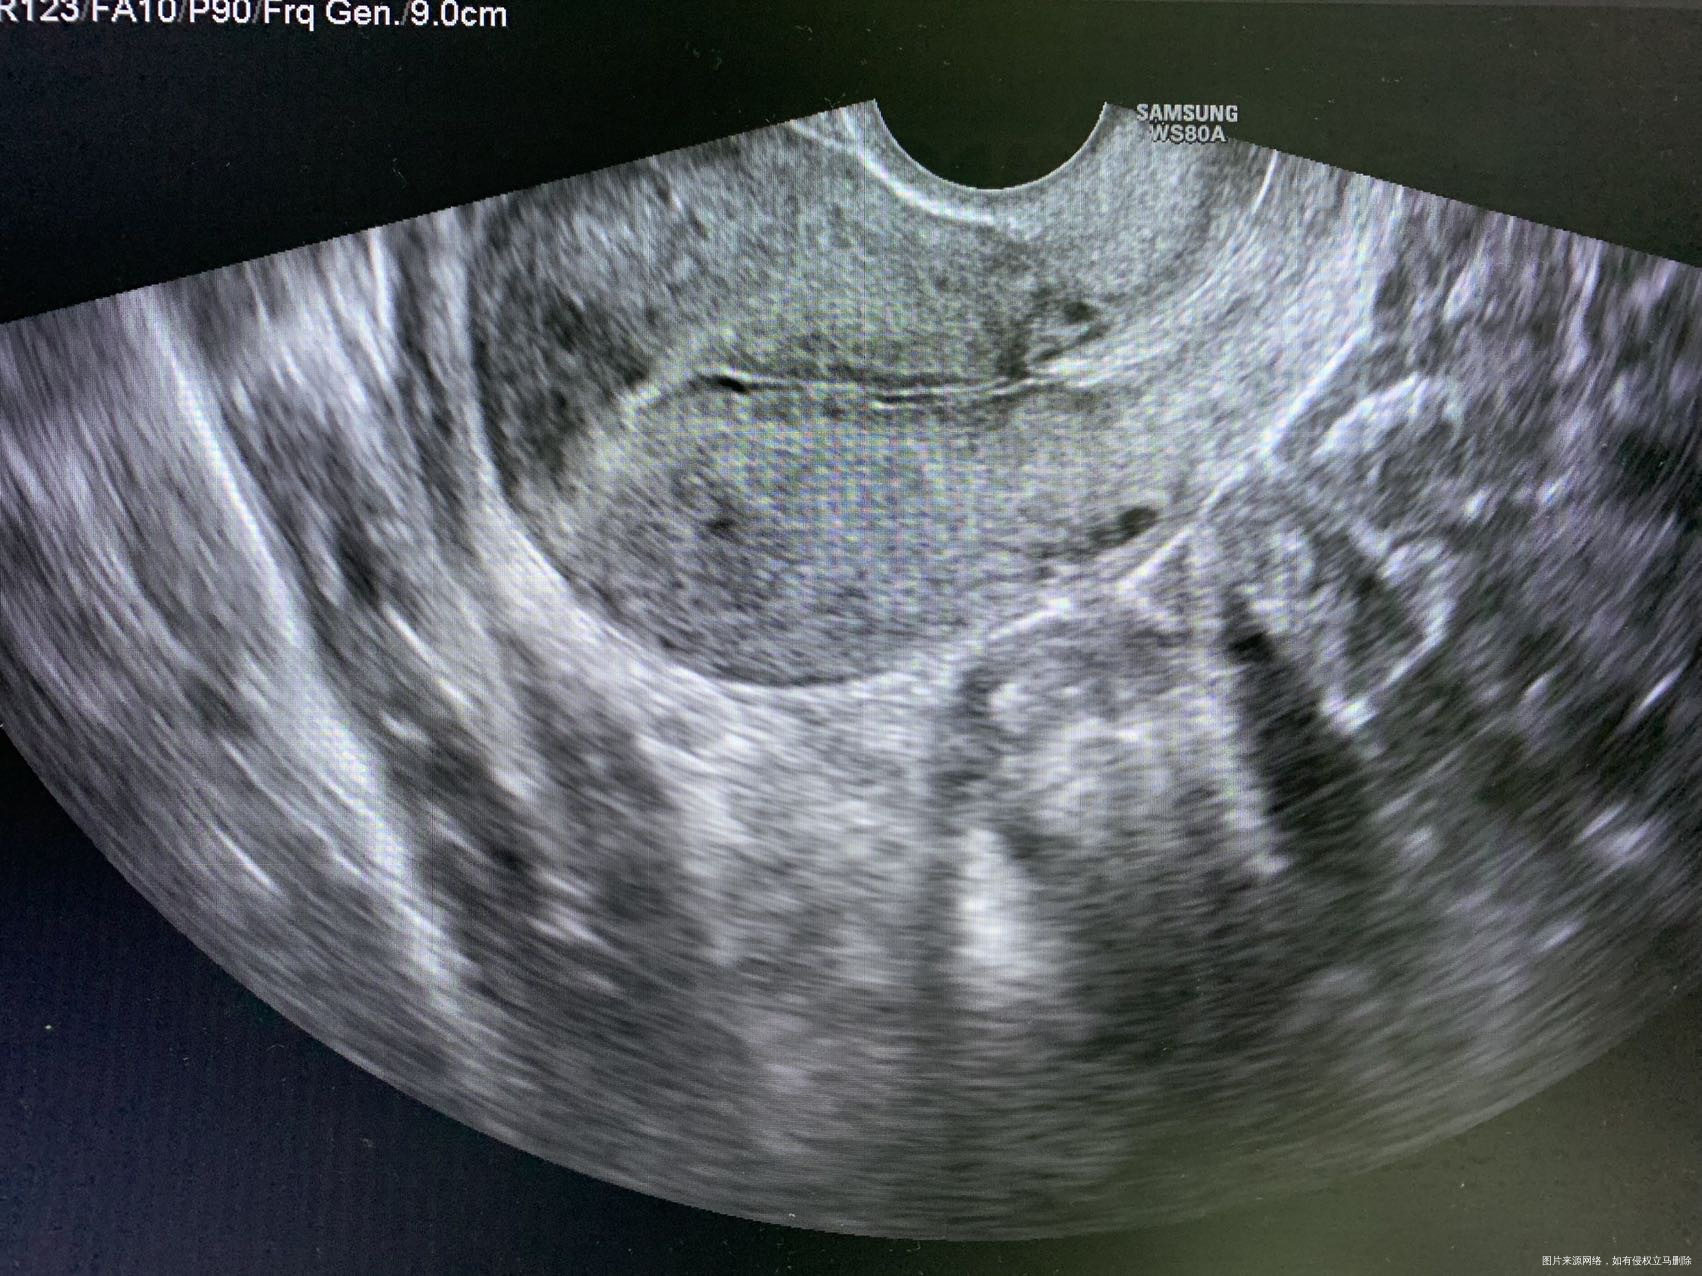

医生帮我看下我重新进入周期了年初四姨妈来了没几天很少量没有了,然后年后去看医生问医生然后做了阴超21号内膜6没有宫腔分离,医生让我礼拜一吃地屈孕酮片吃十天但是吃了第五天就开始来了但是量不多一开始因为吃药原因姨妈颜色咖啡色的,但是后面第五天一坨血浆一样下来,前几天量很少,我现在重新进入周期了,我以前从来没有的,就打促排卵针后面两次阴超有宫腔分离,

宫腔分离与子宫内膜炎症、促排卵、输卵管积液等原因有关系。促排卵周期,遵医嘱用药。

宫腔分离的主要原因可能有宫腔积液。一般是因为炎症引起的,医生让你吃地屈是希望你的内膜好好剥脱一下,利于重新进入周期,你说的一坨血浆一样的,如果有烂肉一样的组织,那就是剥脱的内膜。按医嘱来吧